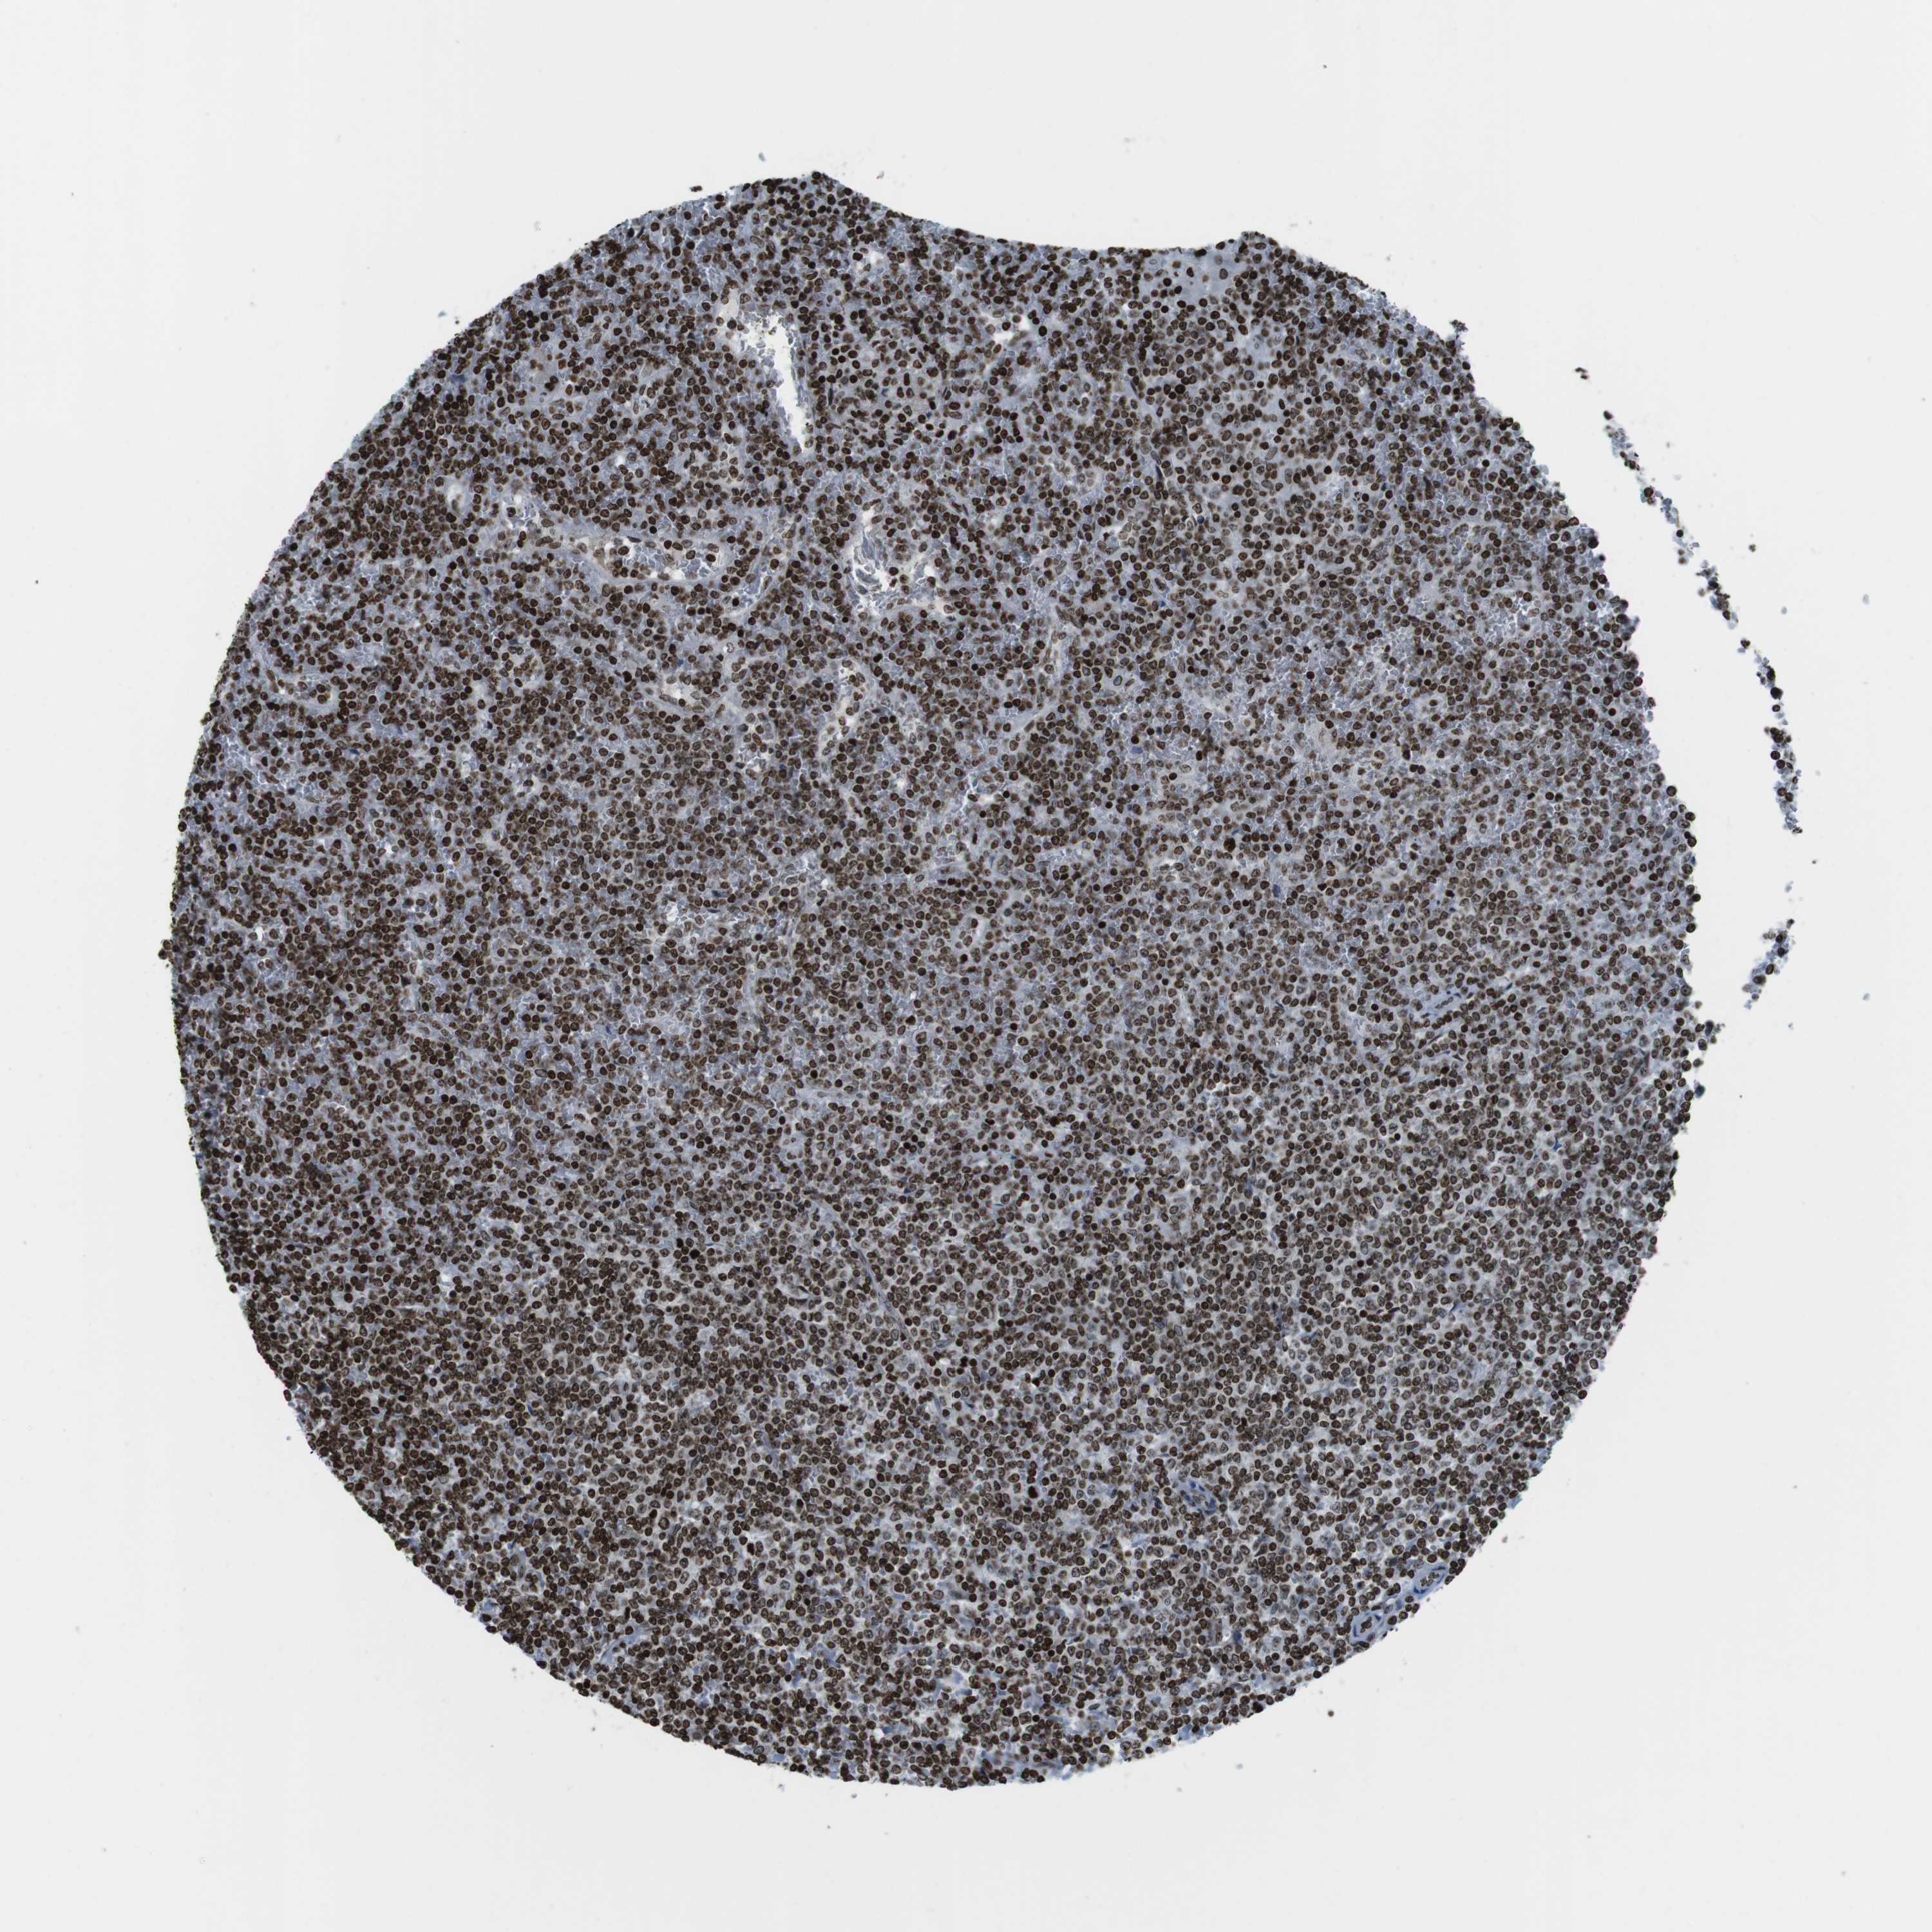

LYMPHOMA - Protein expressioni

A mouse-over function shows sample information and annotation data. Click on an image to view it in a full screen mode. Samples can be filtered based on level of antibody staining by selecting one or several of the following categories: high, medium, low and not detected. The assay and annotation is described here.

Each image is clickable and will lead to virtual microscopy that enables deeper exploration of all samples and also displays staining intensity scores, fraction scores and subcellular localization as well as patient and tissue information for each sample.

Antibody HPA041189

Antibody CAB012242

Staining

High

Medium

Low

Not detected

Intensity

Strong

Moderate

Weak

Negative

Quantity

>75%

75%-25%

<25%

None

Location

Nuclear

Cytoplasmic/membranous

Cytoplasmic/membranous,nuclear

Hodgkin's disease, NOS

Malignant lymphoma, non-Hodgkin's type, High grade

Malignant lymphoma, non-Hodgkin's type, Low grade